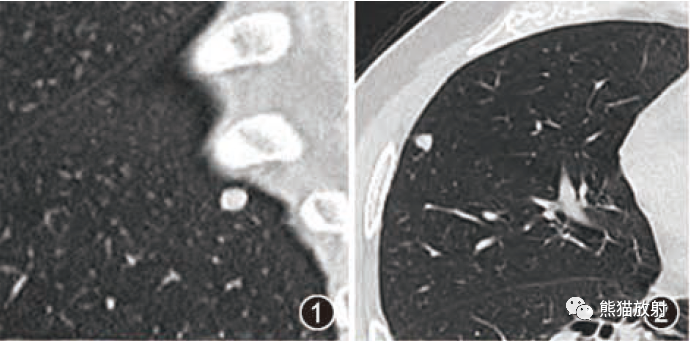

2.病变周围GGO,边界清楚或稍模糊。圆圈征、草帽征、树上蘑菇征等。

8、斑片常伴有结节,边缘清楚GGO或欠清楚。